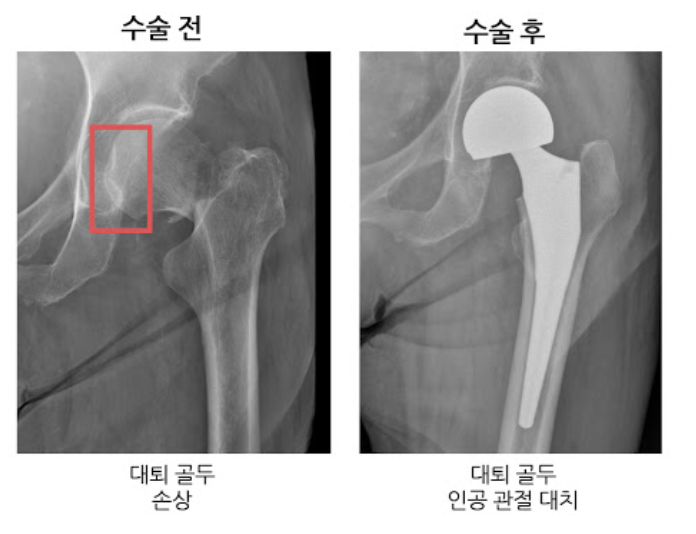

대퇴골두 무혈성괴사

쉽게 말해서 고관절 근처의 혈액순환에 문제가 생겨서 대퇴골 머리 부분에 혈액이 제대로 공급되지않게 됩니다. 이럴 경우 혈액이 공급되지 않아 뼈가 썩게 됩니다.

두번쨰로는 대퇴골두에만 인공뼈를 삽입하여 치환시키는 방법과 세번째로는 관절 부분 전체를 인공관절로 바꿔주는 방법이 있습니다. 이 경우에는 심하게 괴사가 된 경우에 사용하는 방법으로 합병증이 적고 기능개선이 우수하다고 알려져 있습니다.